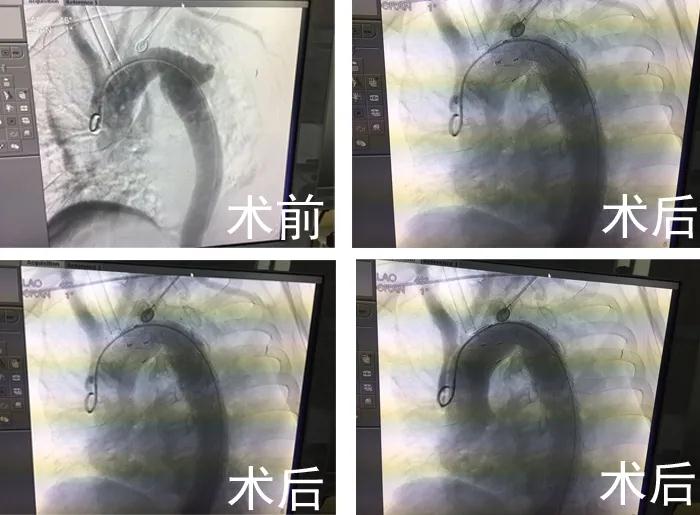

在CCU顏景朋主任、麻醉科陶宏主任的指導(dǎo)下,從股總動(dòng)脈穿刺插入導(dǎo)管至升主動(dòng)脈。造影顯示降主動(dòng)脈左鎖骨下動(dòng)脈開(kāi)口遠(yuǎn)端約1.8cm,外側(cè)有一破口約1.0cm寬,破口周圍假性動(dòng)脈瘤形成,通過(guò)導(dǎo)入胸主動(dòng)脈帶膜支架精確定位到左鎖骨下動(dòng)脈后緣,然后釋放,再次造影,顯示破口封堵成功,手術(shù)順利結(jié)束。